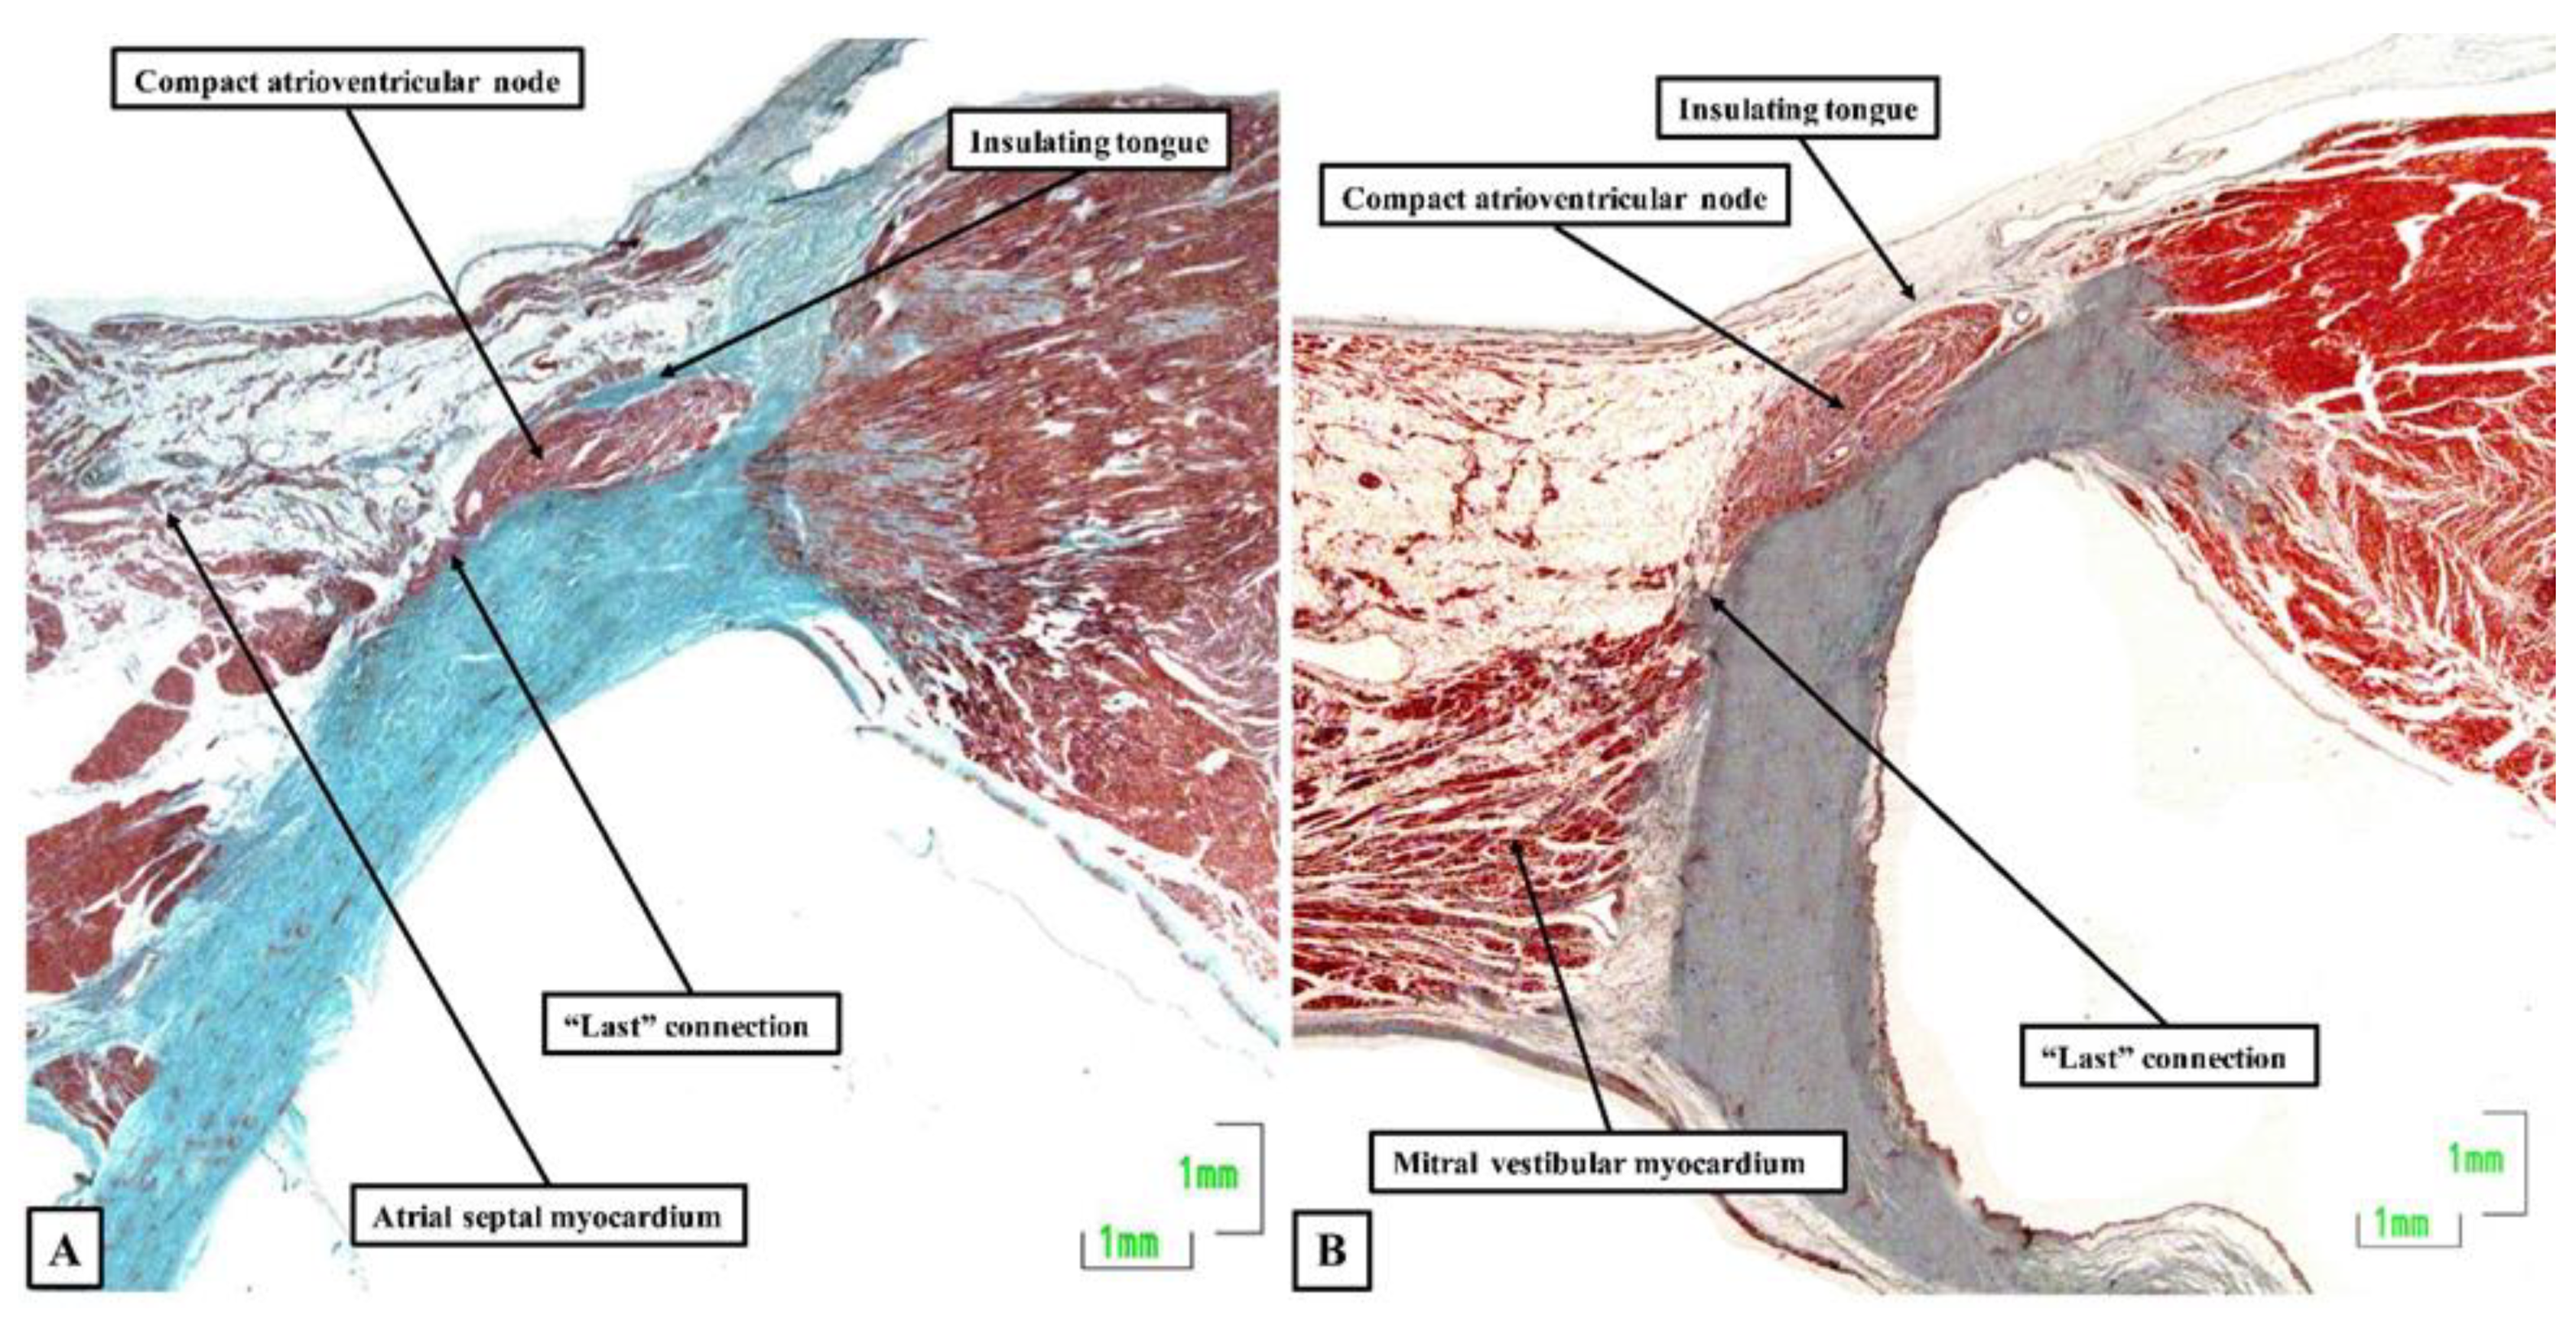

- Anderson, R.H.; Sanchez-Quintana, D.; Mori, S.; Cabrera, J.A.; Back Sternick, E. Re-evaluation of the structure of the atrioventricular node and its connections with the atrium. Europace 2020, 22, 821–830. [Google Scholar] [CrossRef]